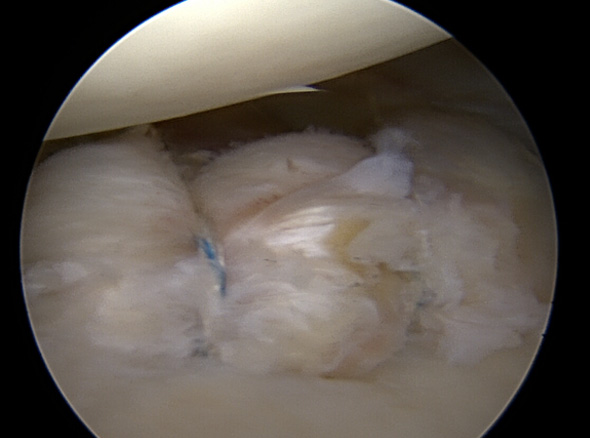

관절 내시경을 통해 파열된 관절와순을 정상적인 모양으로 봉합하여 제 기능으로 회복시켜 줍니다.

재발성 탈구(2회 이상)인 경우

첫 탈구이나 관절와순이 전위되어 있어

재탈구 가능성이 높은 경우

운동선수나 스포츠 매니아는 적극적으로 고려해야 함